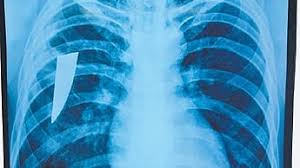

The sharp steel piece caused persistent cough and fever and initially he was misdiagnosed as tuberculosis. Later nn X-ray and CT scan confirmed the object in the lung.